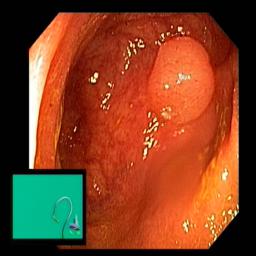

The performance metrics for Edgeconnect and AOTGAN on the validation data after fine-tuning the models, are shown in Table II. In addition to qualitative evaluation, Figure 3 provides example data from the different steps of the PolypConnect pipeline using the EdgeConnect model and the AOTGAN model. Due to obvious visual differences in the generated polyps between the models, we selected the EdgeConnect model as the main polyp inpainting model of the PolypConnect pipeline for further evaluation and qualitative assessment by domain experts.

Figure 3: Sample data used and generated in the different steps of PolypConnect pipeline. (a) - real polyp images, (b) - manually annotated polyp masks, (c) - randomly selected colon images used as input to the final step of PolypConnect, (d) - extracted edge images of row c. (e) - extracted edge images of polyp regions of row a using the masks of row b. (f) - combined edge images of row d and f. (g) - generated polyp on the images of row c using EdgeConnect. (h) - generated samples from AOTGAN.